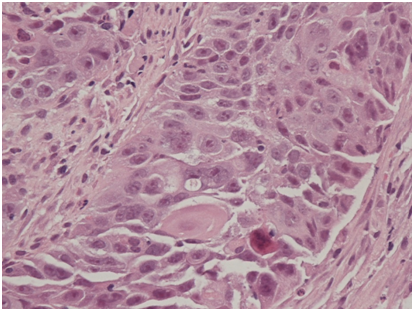

He then underwent full colonoscopic examination, which revealed a large friable and bleeding mass within the caecum (Figure 1). There were no macroscopic areas of ulceration elsewhere within the colon. Histology of the caecal mass reported a moderately differentiated squamous cell carcinoma (Figure 2A). Subsequent immunohistochemistry analysis showed that the tumour cells were strongly positive for CK5/6 and p63, but CK20 and CDX2 negative, consistent with a diagnosis SCC (Figure 2B). Coinciding with this, tumour markers were found to be elevated (CEA 16ug/L).

Figure 2A Haematoxylin and eosin staining (x200 magnification) demonstrating neoplastic squamous epithelium characterised by sheets of cohesive epithelioid cells with enlarged, irregular, ovoid nuclei and prominent nucleoli as well as eosinophilic cytoplasm. Squamous differentiation is demonstrated in the form of intercellular bridges and the presence of keratinised cells.